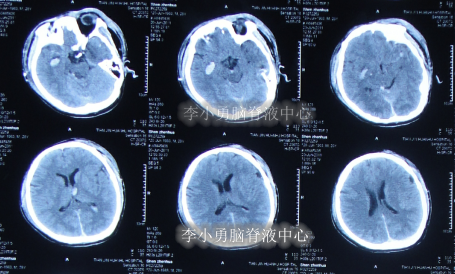

患者于2011年6月20日,因意外车祸致全身多器官损伤昏迷,当天住入天津著名的三甲脑科医院,检查明确颅脑外伤、肺挫伤、骨盆骨折(片子丢失),头部MRI和CT提示颅骨骨折,脑干弥漫性轴索损伤,颅内有出血,水肿(图-1、图-2)。

图-1:2011年6月20日头部MRI

图-2:2011年6月20日头部CT